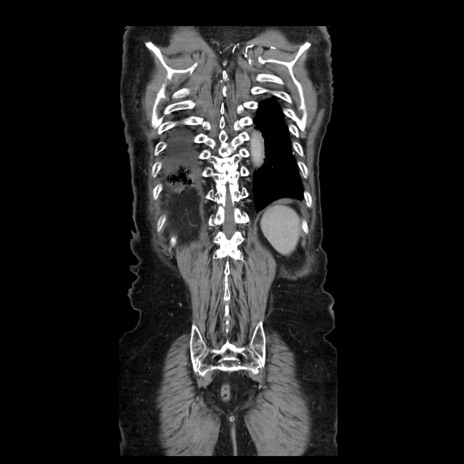

症例21(冠状断像)

【症例】70歳代男性

【主訴】腹痛

【現病歴】肝硬変・肝細胞癌にてかかりつけの方。約9時間前に食後より腹痛出現。症状が徐々に増悪し、嘔吐出現したため来院。

【既往歴】肝硬変、肝細胞癌(RFA、TACE後)

【身体所見】意識清明、表情苦悶様、BT 36℃、BP 129/78mmHg、P 88bpm、SpO2 97%(RA)、右上腹部から心窩部にかけて圧痛あり、反跳痛なし、筋性防御あり。

【データ】WBC 5800、CRP 0.16